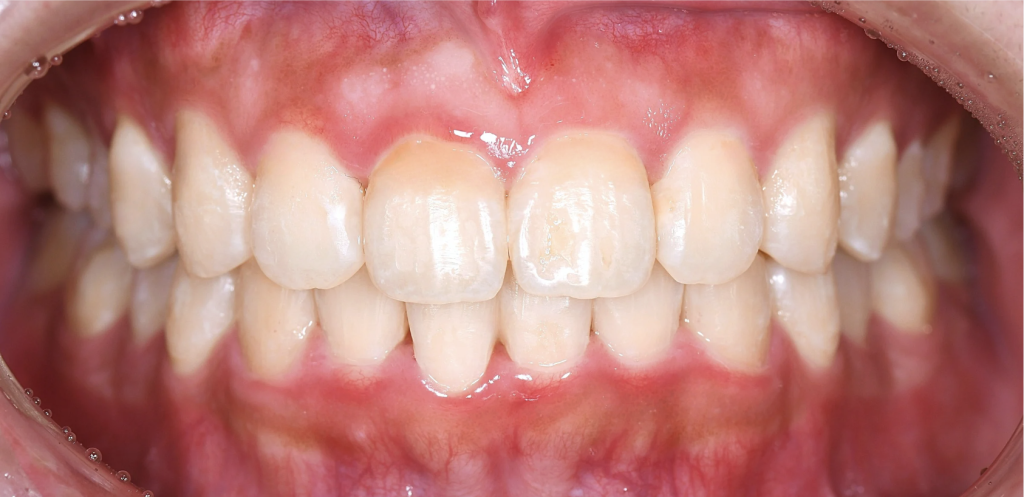

上下ともに狭窄歯列、下顎前歯には叢生(歯のガタつき)、上顎前歯の突出感が認められました。

また、やや上の前歯が下の前歯に覆い被さり、噛み合わせが深い(ディープバイト)傾向もあり、奥歯への負担が強くかかる噛み合わせでした。

また、ディープバイト改善のため、上下の前歯の圧下(顎の骨の中に埋め込む)を行い、適切な前歯の噛み合わせを作りました。